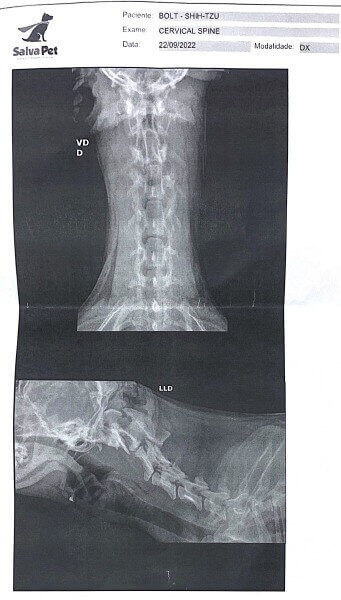

Família de Jundiaí precisa de ajuda para cirurgia de cachorrinho

Bolt tem apenas 10 meses e após um acidente doméstico, acabou ferindo a coluna e precisa de cirurgia.